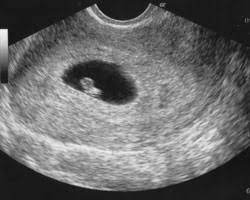

Transvaginal 6 Semanas So Com Saco Gestacional Maio De 2019 Babycenter

6 Semanas E Apenas Saco Gestacional E Vesicula Vitelina Aparente Maio De 2020 Babycenter